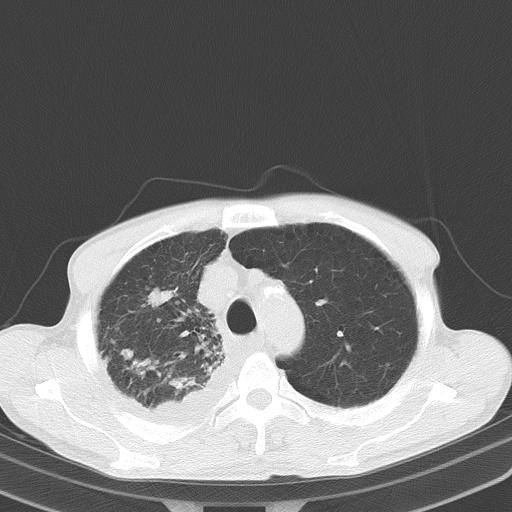

男性 75  咳嗽 一周前发热最高达39

右肺继发型tb并右侧tb性胸腔炎,右侧胸腔大量积液并右下肺膨胀不全,慢支肺气肿、多发肺大泡。建议抽胸水实验室检查并复查排除恶性在占位。

右上肺继发型肺结核,右胸腔中等量积液。

左上肺大泡。

1)右肺继发型肺结核。2)左肺胸膜下多发性肺大泡。3)右侧胸腔积液。